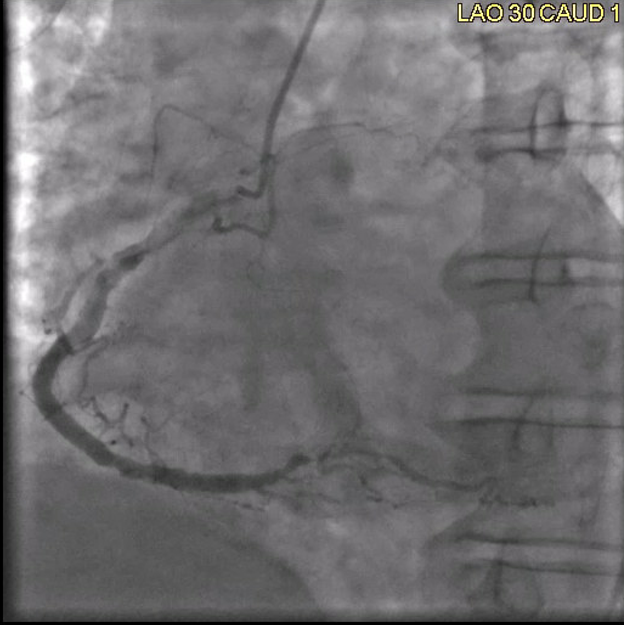

A left heart catheterization revealed a pattern of apical ballooning consistent with stress cardiomyopathy (Figure 2) and a severely depressed left ventricular ejection fraction of 10%. Significant obstructive triple-vessel coronary artery disease was noted with poor collateral circulation (Figures 3-4). No evident left ventricular outflow obstruction. An intra-aortic balloon pump (IABP) was placed, while coronary interventions were held at that time. On the second day of hospitalization, the patient developed intermittent high-grade AV block with hemodynamic instability which progressed to persistent complete heart block (CHB) (Figure 5). Medical management and transcutaneous pacing were initiated until transvenous pacing was achieved. The IABP was later exchanged for an Impella device due to refractory cardiogenic shock and worsening vasopressor requirements.

Figure 3: Coronary angiogram, left anterior oblique view, mild RCA beading, severely diseased RPDA.